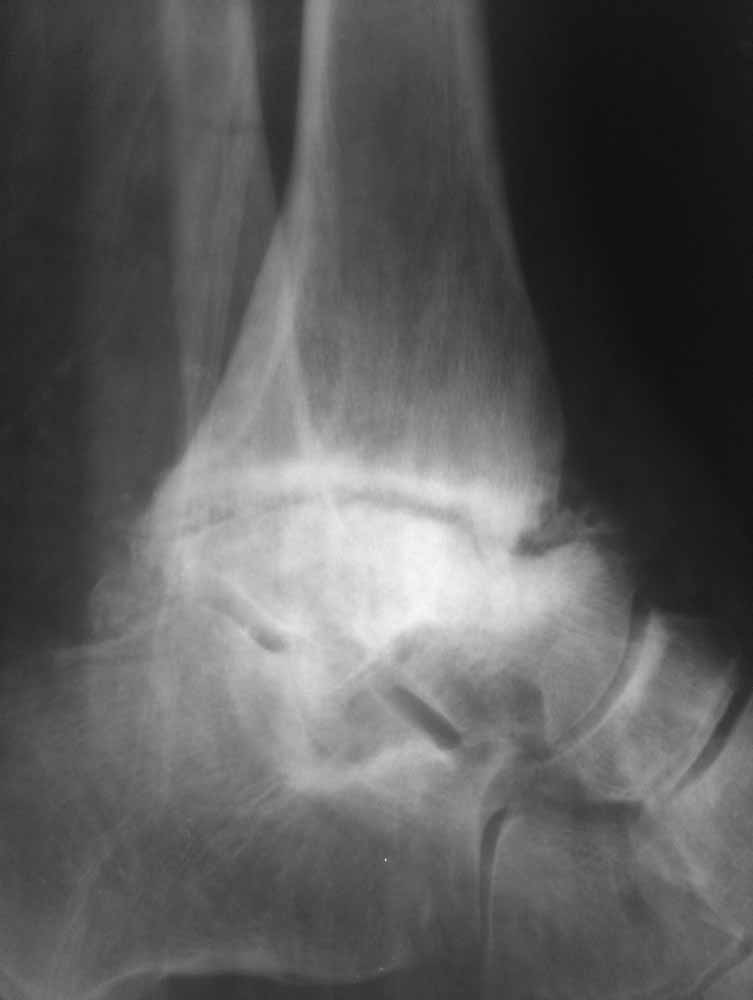

Опять прошу прощения за качество фото, но принципиальные моменты мне кажется, что видны.

Из того, что я вместе с лучевыми диагностами разглядел - нельзя исключить остеомиелит (?) - есть краевая реакция, куча элементов, похожих на секвестры. Смущает полное отсутствие местной и системной реакции - к анализам не придраться.

Про оперативное - думаем об артродезе правого голеностопа (пока и там ничего не съехало - боль в правом голеностопе усилилась из-за увеличения нагрузки), а слева (где как раз и есть некроз тарана и пилона) - открыть, чистить, бусы с антибиотиком, максимально коррекция сразу + аппарат.

Про опухоли - склоняюсь к мысли, что все таки может быть какое-то из последствий лучевой болезни (31 явка на ЧАЭС) (?!)...